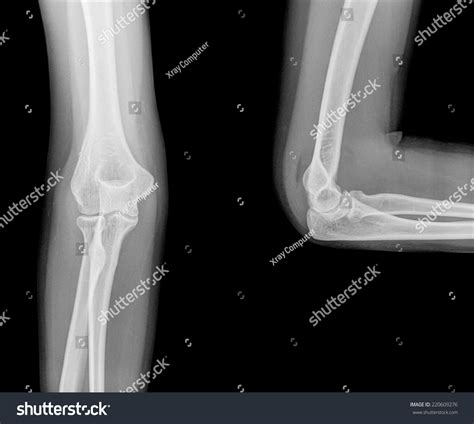

Diagnosing nursemaid elbow typically involves a physical examination by a healthcare provider. The provider will assess the child's arm and elbow for signs of injury and may perform a gentle manipulation to confirm the diagnosis. In some cases, a Nursemaid Elbow Xray may be ordered to rule out other potential injuries, such as fractures or dislocations. However, X-rays are not always necessary for diagnosing nursemaid elbow, as the injury does not typically show up on imaging studies.

In some cases, nursemaid elbow may be mistaken for other injuries, such as fractures or dislocations. It is important to seek medical attention if your child experiences pain or limited movement in the elbow, even if you are not sure what caused the injury. A healthcare provider can perform a thorough evaluation and order a Nursemaid Elbow Xray if necessary to rule out other potential injuries.